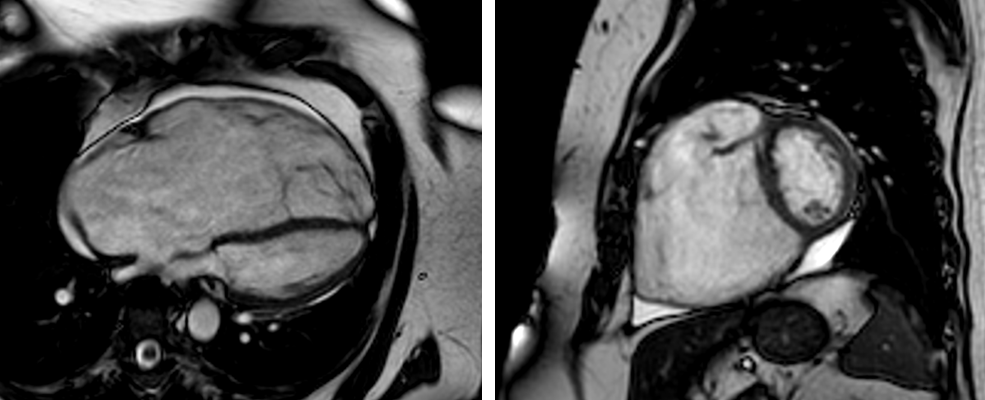

Mit Hilfe von planimetrischen Verfahren (Bestimmung der Klappenöffnungsfläche) sowie Phasen-Kontrast-Sequenzen kann sowohl die morphologische als auch funktionelle Quantifizierung von Herzklappenerkrankungen (z.B. Aortenklappen-Erkrankungen) erfolgen. Nach erfolgter minimalinvasiver Klappenimplantation kann die Funktion der Herzklappe sowie die Struktur des Myokards verlaufsbeurteilt werden.

Vor und nach Aortenklappenersatz Darstellung großer Gefäße